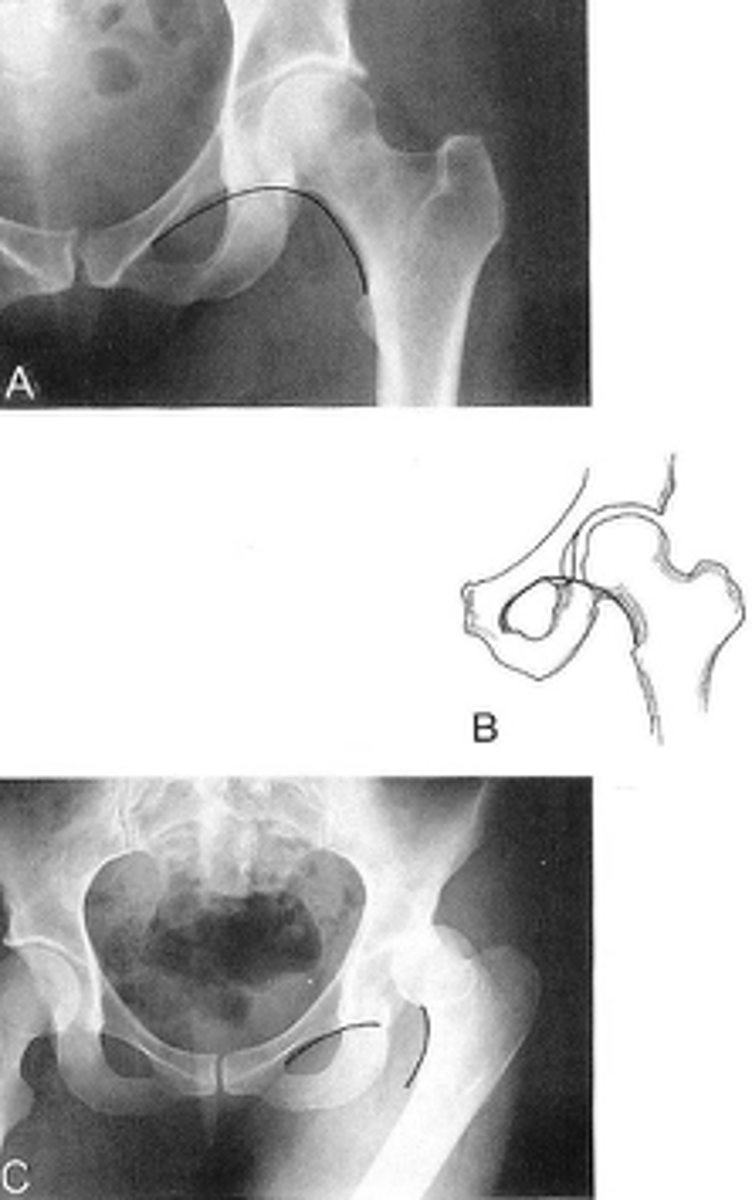

Shenton's line

ID measurement

<p>ID measurement</p>

- AP hip

- AP pelvis

What views are used to see Shenton's line?

- Smooth arc along femoral neck

- Obturator foramen

Shenton's line landmarks

Continuous and smooth

Shenton's line normal measurements

<p>Shenton's line normal measurements</p>

- Hip dislocation

- Femoral neck fracture

- Slipped epiphysis

Clinical significance of Shenton's line

<p>Clinical significance of Shenton's line</p>